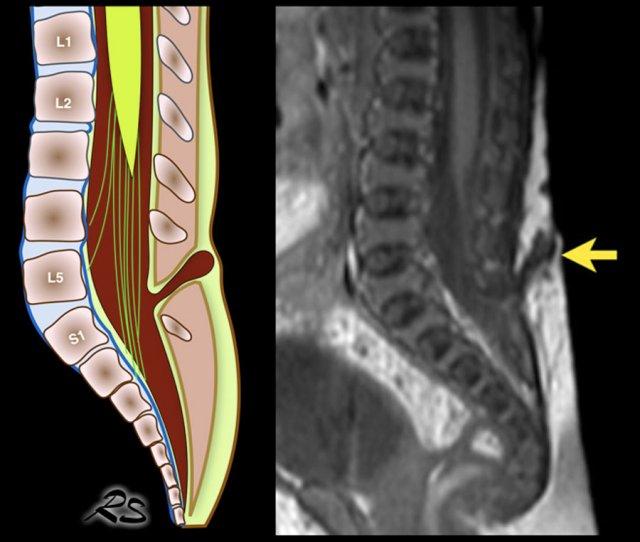

Vị trí của nón tủy

Vị trí bình thường của nón tủy là ở L1.

Nón tủy không được nằm dưới mức L2.

Cách tốt nhất để xác định vị trí của nón tủy là nhận diện khớp thắt lưng-cùng tại góc ưỡn giữa các đốt sống thắt lưng và cùng (mũi tên).

Có thể hữu ích khi gấp và duỗi khung chậu để quan sát điểm chuyển động của xương cùng.

Ở trẻ sơ sinh này, khớp thắt lưng-cùng khó nhận diện hơn do không có góc nhọn rõ ràng.

Các số thứ tự chúng tôi đã đánh dấu có thể không chính xác.

Nếu còn nghi ngờ, hãy chụp ảnh toàn cảnh hoặc ảnh kép của cột sống thắt lưng-cùng và so sánh số đốt sống đếm từ dưới lên với phim X-quang thẳng nghiêng.